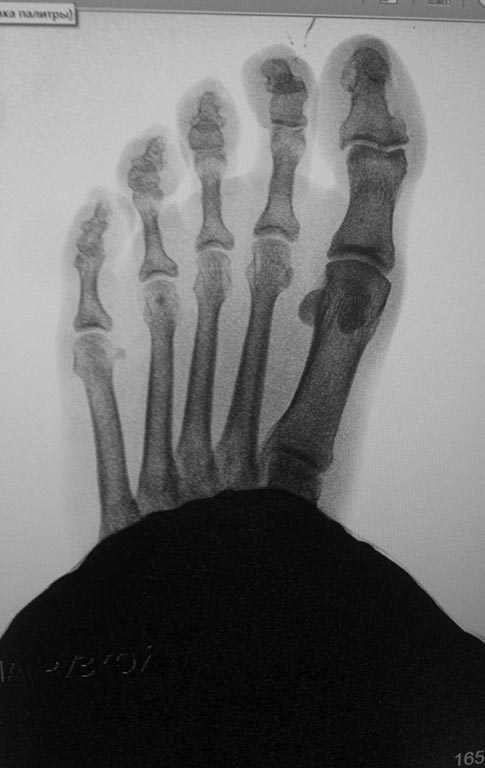

Обратилась женщина с жалобами на выраженную боль, натоптыши в области проксимальных межфаланговых суставов V пальцев стоп.

У больной имеется деформация Тейлора ( угол М4М5 11.5 с двух сторон под нагрузкой). В области пятого плюснефалангового сустава деформация. Боли, гиперемии нет.

Достаточно ли в данном случае остеотомии пятой плюсневой кости с нормализацией угла М4М5 и укорочением?

Если еще актуально, то болезни портных тут не видно. А боль может быть связана с давлением на мозоли, образовавшиеся поверх выпуклостей на тыльнолатеральной поверхности головок основных фаланг пятых пальцев или оснований средних фаланг. Ситуация достаточно частая. Сориентироваться легко под ЭОПом. Или с помощью рентгена с метками, если нет ЭОПа. Можно инъекционную иглу воткнуть до упора в выпуклость и сделать снимок. Чтобы избежать позиционных искажений. А потом убрать эти выпуклости. Чрескожно или открыто, в зависимости от возможностей.